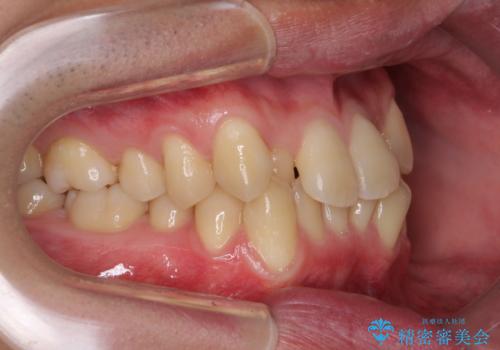

- 前歯のがたつきが気になるとのことで来院されました。

骨格的なところと、上下の歯の大きさのことを考慮して、下の前歯を1本抜歯し、インビザラインにて矯正治療することとなりました。

上の前から2番目の歯がもともと小さかったため、最後にかぶせ物を装着することで、自然な仕上がりにできました。